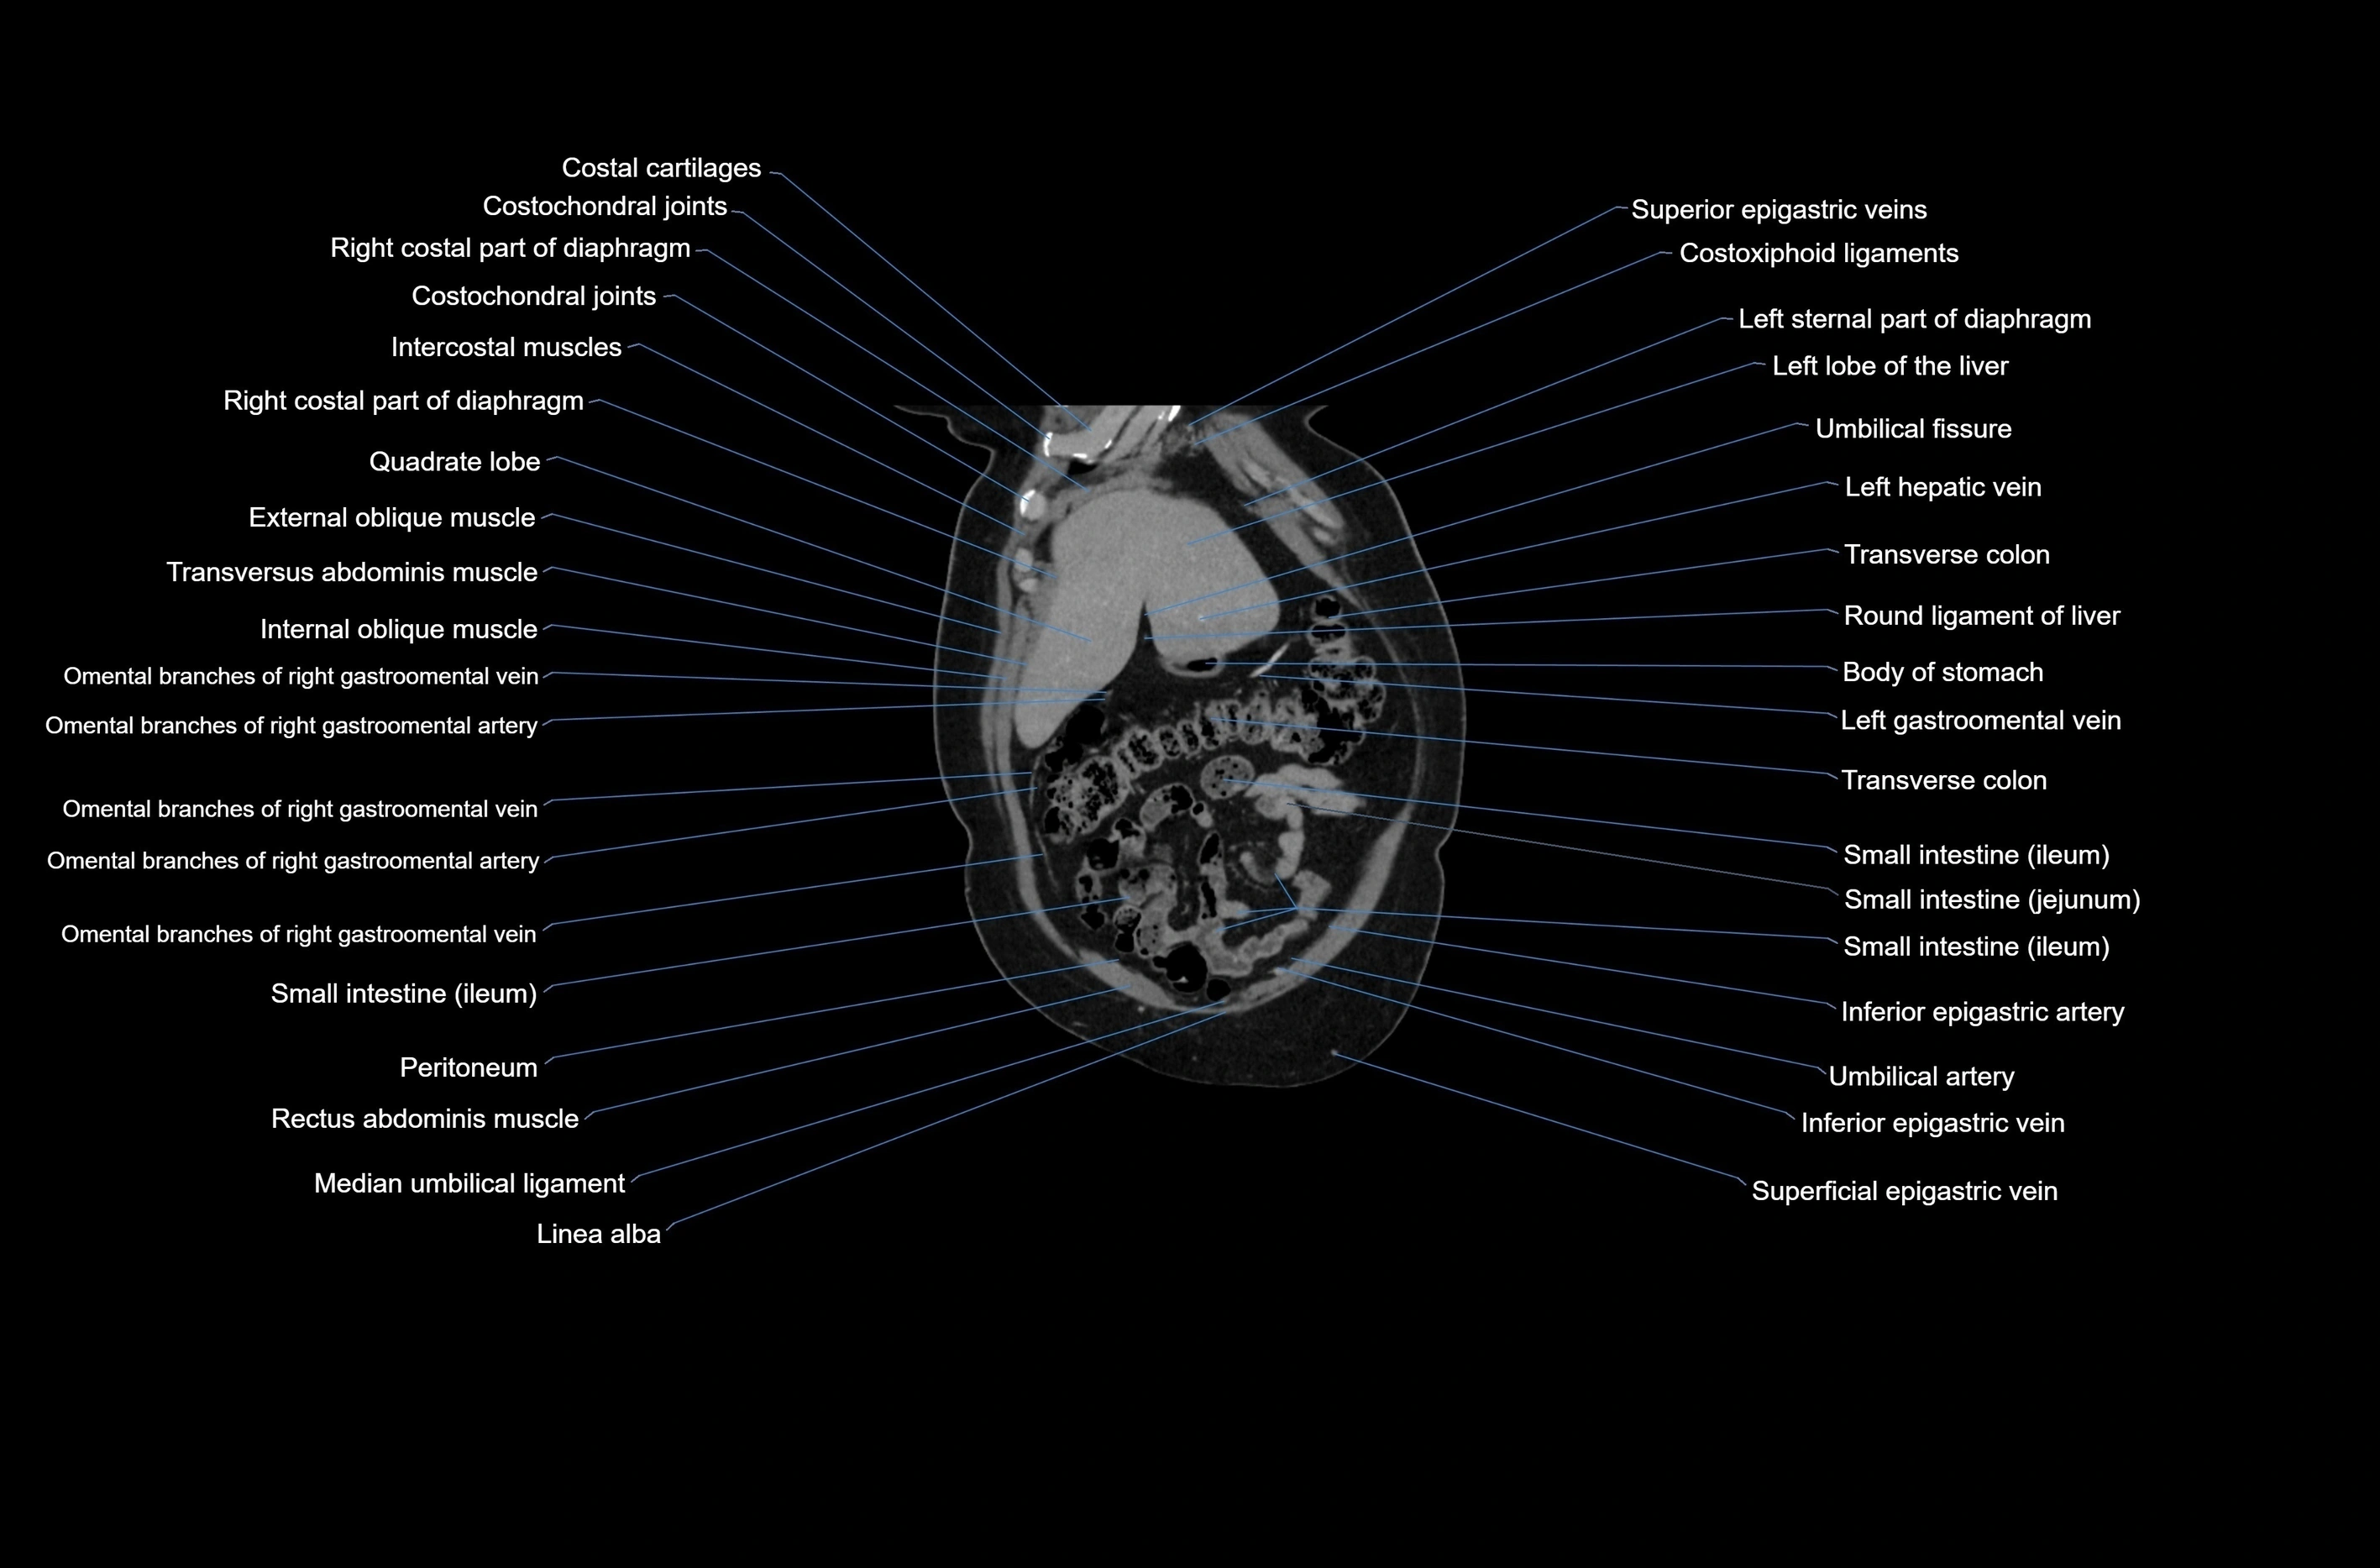

CT images